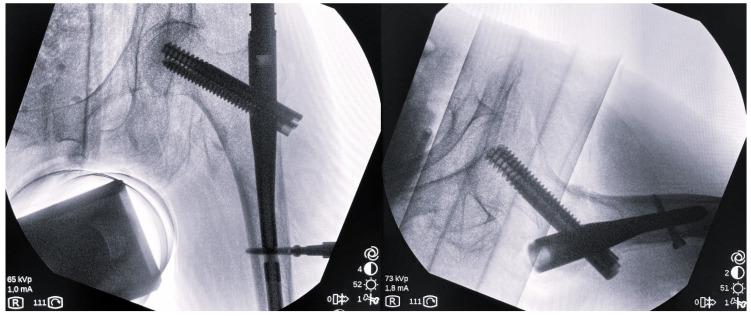

Rotational malformation after intramedullary nailing of intertrochanteric fractures is a relatively common, possibly severe, and difficult-to-detect complication, since intraoperative radiographic imaging allows for the assessment of the quality of reduction in the frontal and sagittal planes, but not in the transverse plane. The purpose of this study is to evaluate the rotational malalignment after intramedullary nailing of intertrochanteric fractures and to investigate a possible connection with specific patients' or fractures' characteristics. 74 patients treated with intramedullary nailing due to an intertrochanteric fracture underwent a postoperative CT of the pelvis-hips and knees. The value of the anteversion was measured both in the operated-on (angle 1) and in the healthy hip (angle 2) based on the technique described by Jeanmart et al. and the difference in anteversion (D angle = angle 1 minus angle 2) was calculated. A positive D angle indicated the presence of excessive internal overcorrection of the distal fragment during fracture reduction, while a negative D angle indicated the presence of excessive external overcorrection. The absolute value of the D angle represents the postoperative difference in anteversion between the two hips. The patients were divided into three groups according to this value: group A, with D < 5° (physiological difference); group B, with 5° < D < 15° (acceptable rotational alignment); and group C, with D ≥ 15° (rotational deformity). Group A constitutes 56.8%, group B 12.2%, and group C 31.1% of the study population. Overall, 79.7% of the patients presented a positive angle D, while, for group C, the percentage was even higher at 91.3%. According to the AO/OTA classification system, 37.8% of the cases were stable fractures, 47.3% were unstable fractures, and 14.9% were reverse oblique fractures. Based on our analysis, the type of fracture has a serious impact on the rotational alignment, since the statistical significance of the mean angle D for the three types of fracture is reliable ( = 0.029). Stable fractures present the lowest anteversion difference values, while reverse oblique fractures present the highest difference. Our study reveals that the percentage of rotational malalignment after the intramedullary nailing of intertrochanteric fractures remains high (31.1%), despite the proper use of radiographic imaging during the intraoperative fracture reduction. In most cases (91.3%), this malalignment appears to be a matter of internal overcorrection. A clear correlation between hip's rotational deformity and patients' functional outcome has yet to be proven, and constitutes our objective in the near future.

股骨转子间骨折髓内钉固定术后的旋转畸形是一种相对常见、可能严重且难以察觉的并发症,因为术中影像学检查仅能评估矢状面和冠状面的复位质量,而不能评估横断面的复位质量。本研究旨在评估股骨转子间骨折髓内钉固定术后的旋转对线不良,并探讨其与特定患者或骨折特征之间的可能联系。

74 例股骨转子间骨折患者接受了髓内钉治疗,术后均行骨盆-髋关节和膝关节 CT 检查。根据 Jeanmart 等人描述的技术,测量了患侧(角度 1)和健侧(角度 2)的前倾角,并计算了前倾角的差值(D 角=角度 1 减去角度 2)。D 角为正值表示骨折复位时远端骨折块存在过度内纠正,D 角为负值表示存在过度外纠正。D 角的绝对值代表术后双侧髋关节前倾角的差异。根据这一数值,将患者分为三组:A 组,D < 5°(生理差异);B 组,5° < D < 15°(可接受的旋转对线);C 组,D ≥ 15°(旋转畸形)。A 组占研究人群的 56.8%,B 组占 12.2%,C 组占 31.1%。总体而言,79.7%的患者 D 角为正值,而 C 组的这一比例甚至更高,为 91.3%。根据 AO/OTA 分类系统,37.8%的病例为稳定骨折,47.3%为不稳定骨折,14.9%为反斜骨折。根据我们的分析,骨折类型对旋转对线有严重影响,因为三种类型骨折的平均 D 角具有统计学意义( = 0.029)。稳定骨折的前倾角差值最小,而反斜骨折的差值最大。